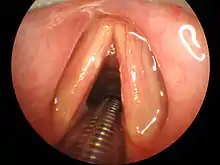

A video laryngoscope image depicting successful intubation with the endotracheal tube successfully placed between the vocal cords

Video Laryngoscopy

Multiple intubation tools are now available with built-in video technology, also known as video laryngoscopy.[9] The GlideScope model utilizes a curved laryngoscopic blade with an integrated camera connected to a large external monitor. The McGrath model has a compact design with a small display directly attached to the laryngoscopic blade. The operator introduces the video laryngoscope through the mouth with a technique similar to direct laryngoscopy. The larynx and vocal cords are visualized via the camera and the operator is able to pass the endotracheal tube through the vocal cords and into the trachea under direct visualization on the video monitor.[9] Studies have shown that when compared to direct laryngoscopy, video laryngoscopy resulted in fewer failed intubation attempts, especially in patients with known difficult airways.[11] Limitations of video laryngoscopy exist and prevent the exclusive use of this method over direct laryngoscopy. Excessive blood and saliva in the airway can cover the camera lens on the video laryngoscope and obscure effective visualization of the anatomy, preventing effective intubation attempts. This is of importance in patients with trauma to their airway, increasing the amount of blood present, and patients taking sialogogues, or drugs that increase the flow of saliva.[12]